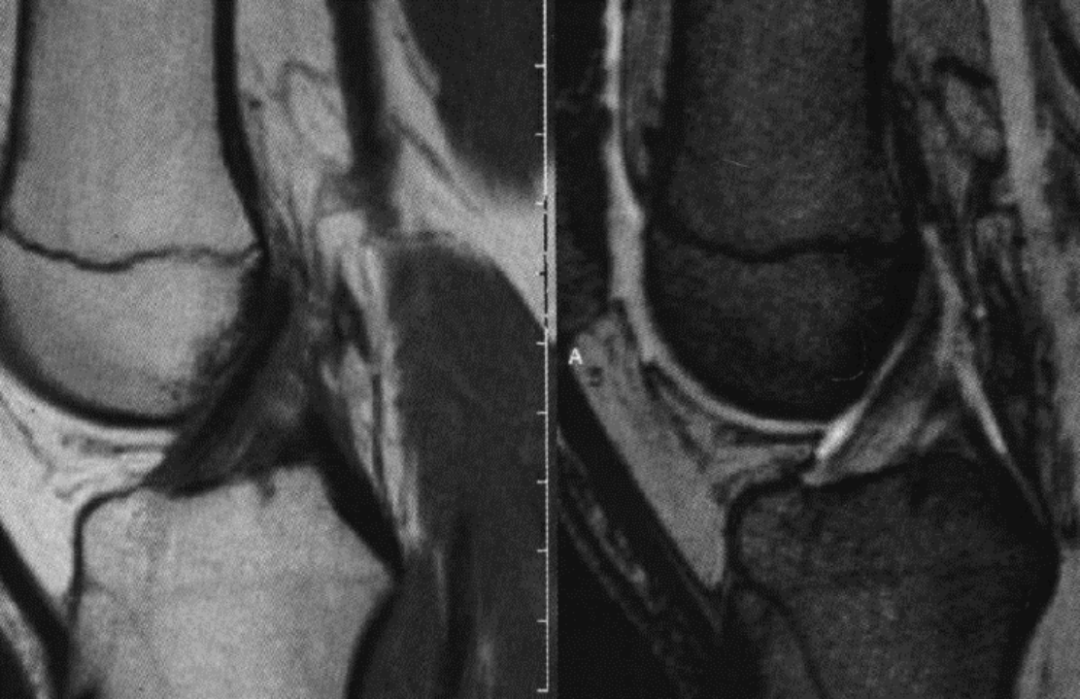

男 40 岁,正常前交叉韧带,扇形,前为低信号,后为中等信号纤维束

男,64 岁,右侧前交叉韧带损伤,止点撕脱骨折

女,50 岁,胫骨髁间隆突撕脱骨折,前交叉韧带部分撕裂